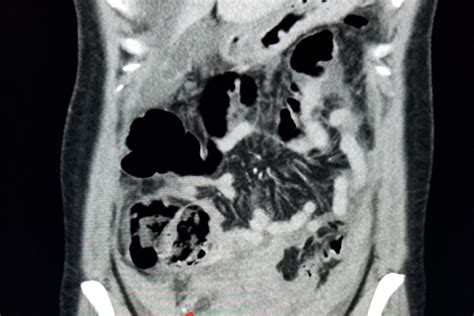

Abdomen/Pelvis 10-20

However, it’s important to note that the level of radiation exposure varies depending on the type of CT scan and the area of the body being scanned. For example, a CT scan of the head exposes the fetus to less radiation than a CT scan of the abdomen or pelvis.

The radiation dose from a CT scan can vary significantly depending on the type of scan and the area of the body being imaged. The following table provides an approximate range of radiation doses for different types of CT scans:

Type of CT Scan Approximate Radiation Dose (mGy)

Full Body 30-40

It’s important to note that the risk to the fetus depends not only on the radiation dose but also on the stage of pregnancy. The first trimester is the most critical period, as this is when organogenesis occurs. The risks decrease as the pregnancy progresses.